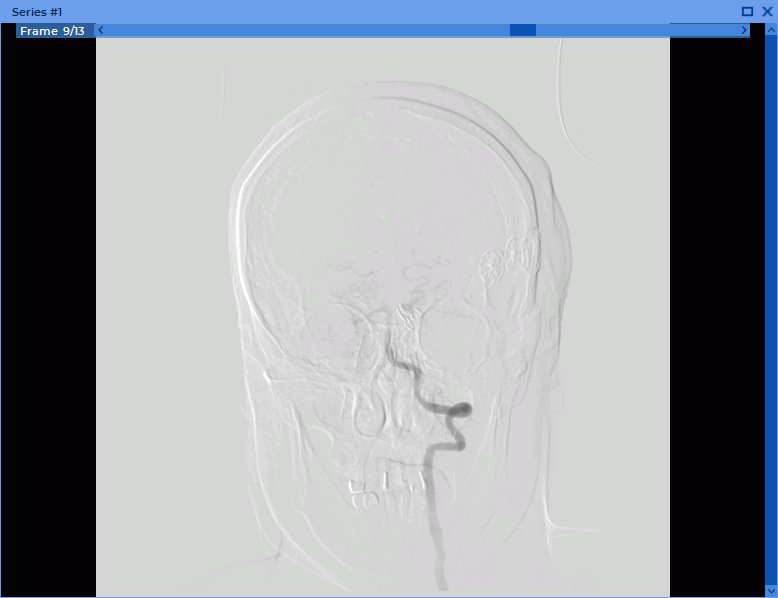

2.29. DSA Mode

Using the DSA mode you can process multiphase and multiframe series with a varying concentration of a contrast agent, subtracting images in such a way that the tissues containing contrast are best seen. Applicable to series with CT, MRI and X-ray modalities.

3. Scroll through the frames by moving the slider or rotating the mouse wheel, hovering the cursor over the scroll bar on the Frame Scroll Bar (Fig. 2.88).